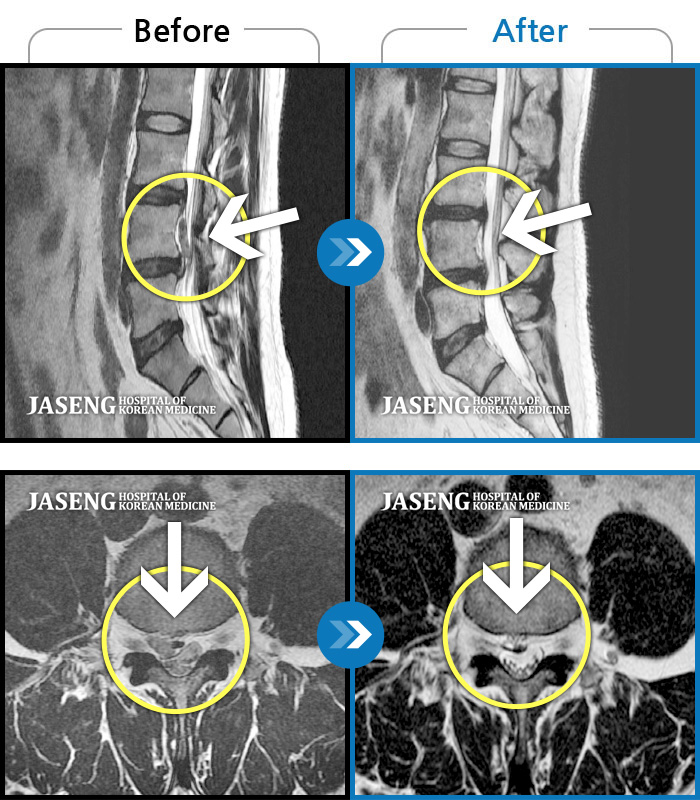

허리디스크

도움받은 사례

강남 · 강만호 원장

허리통증이 심해서 숙이기 어렵고 차에서 내리기 힘들었습니다.

촬영시기

2021.01.06 ~ 2025.03.10

2025.03.20

조회수 13,021